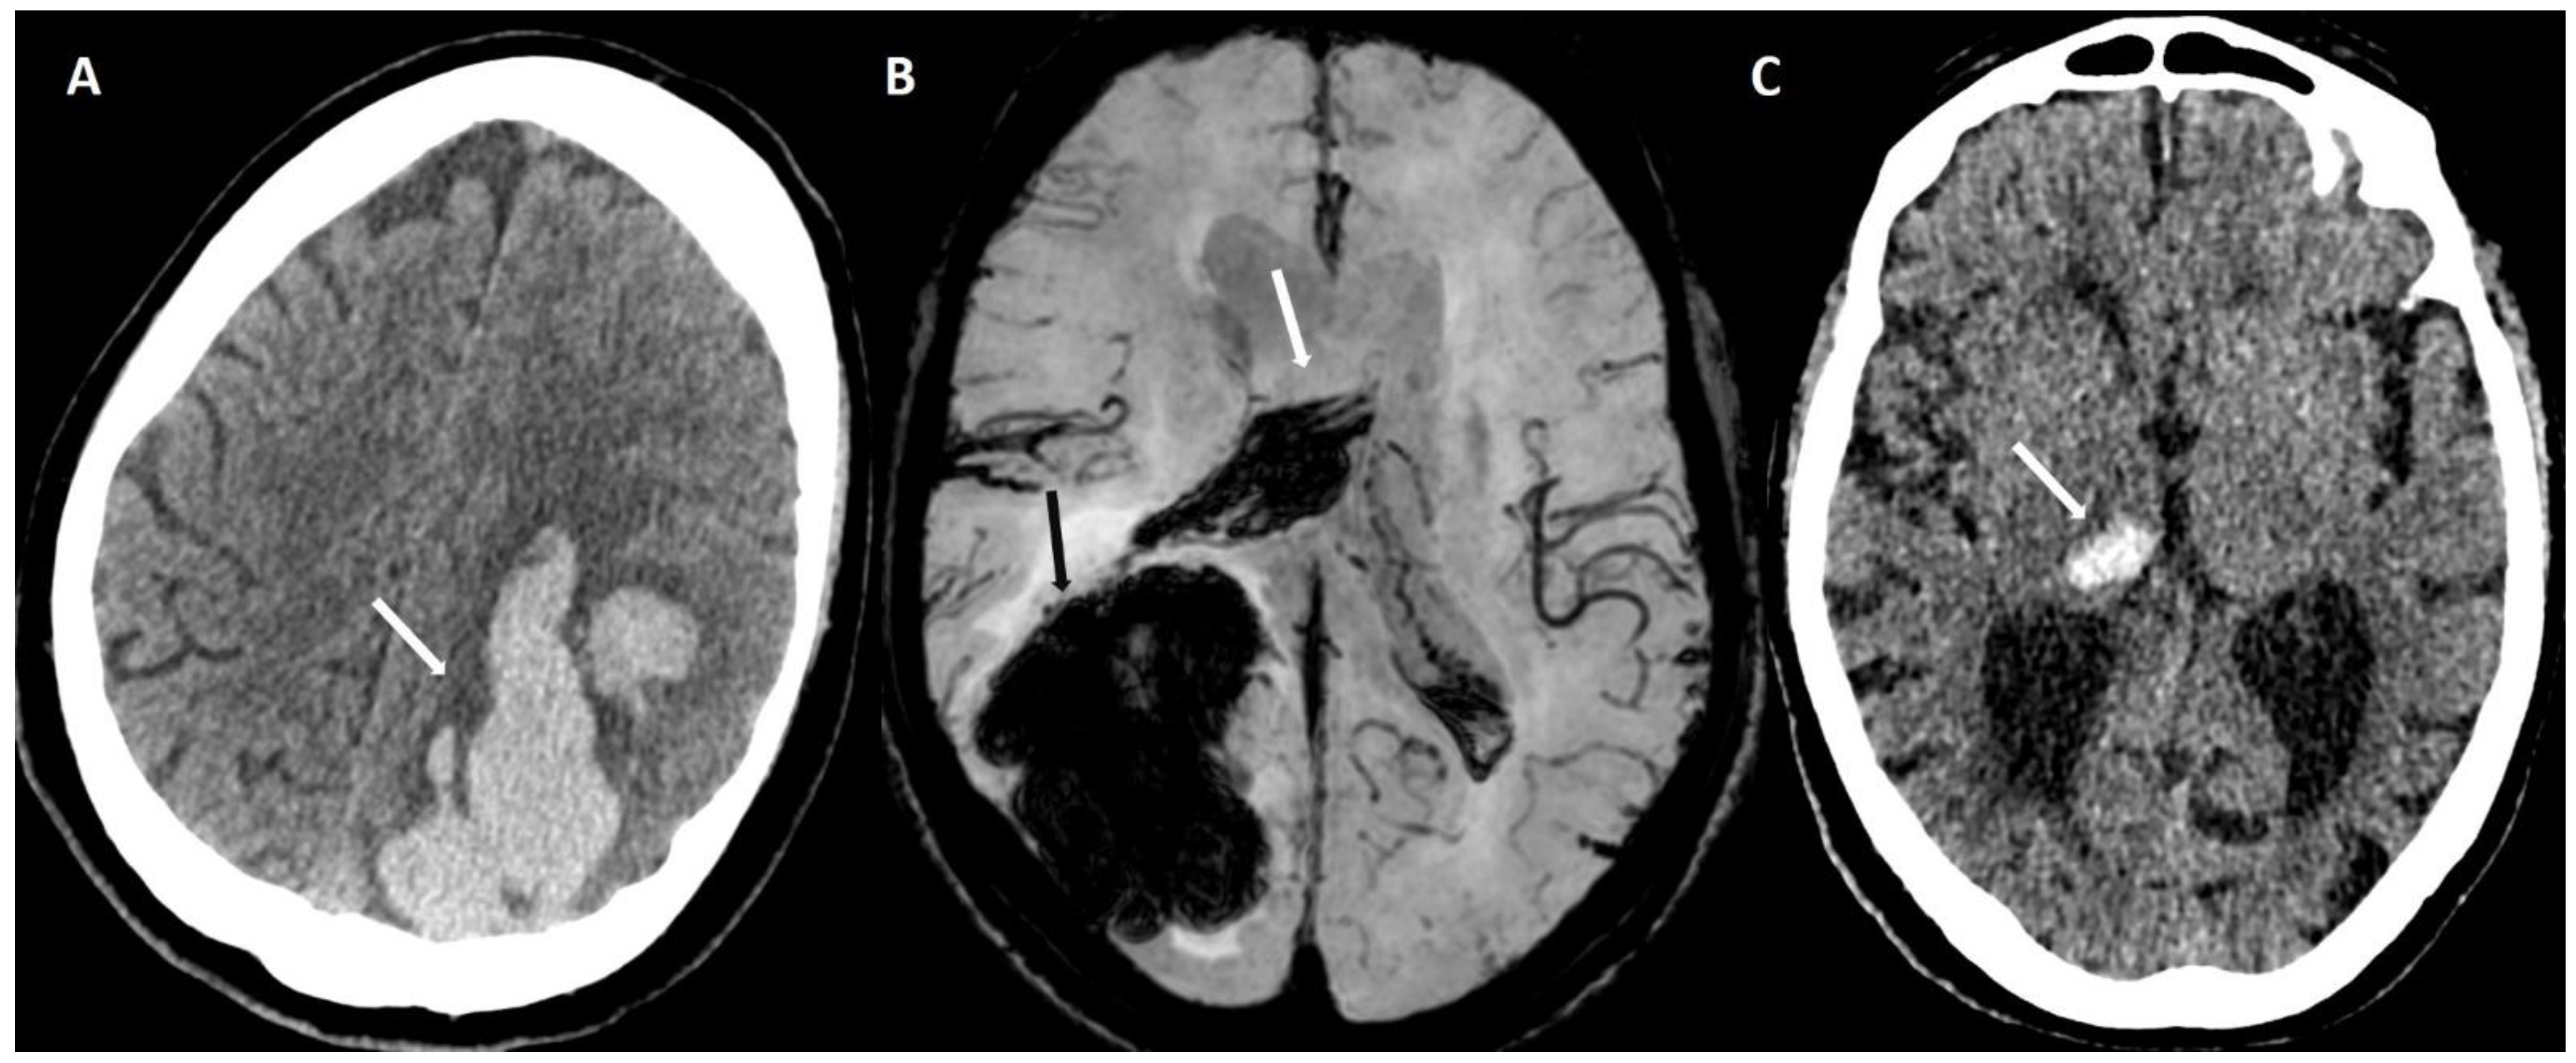

5.1.1. Lobar Hemorrhages

5.1.3. Convexity Subarachnoid Hemorrhage

5.1.4. Cortical Superficial Siderosis

6.1. Finger-like Projections

6.2. Subarachnoid Extension of Lobar Hemorrhage